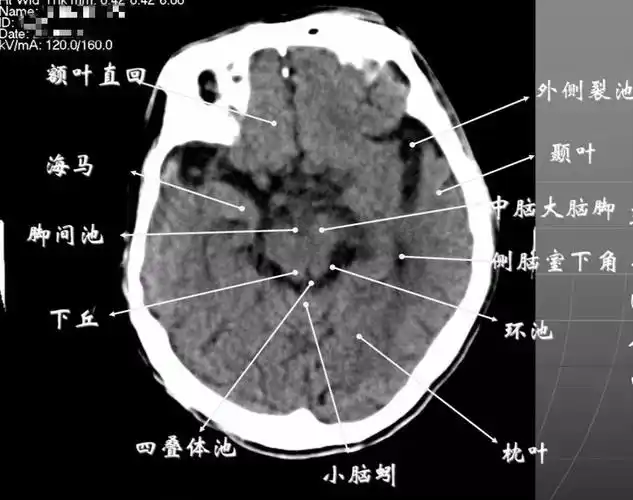

详细标注版——颅脑ct正常解剖图谱_中央_小脑_纤维

简明又详细的头部ct读片详解,收藏!